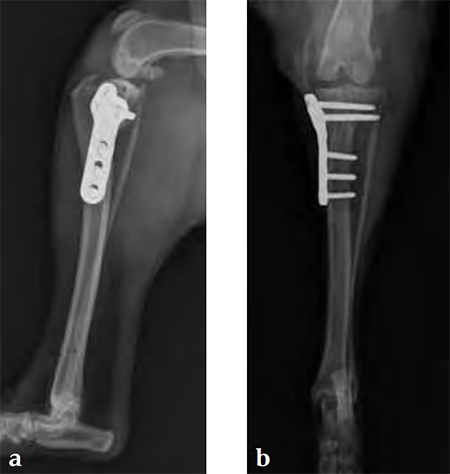

Case 1: English bulldog

(Case provided by Brian Beale, Houston, USA)

A 4-year-old, female, spayed, 33 kg English bulldog had a CrCL tear and a medial patellar luxation. The small stature 3.5 mm TPLO plate was perfect for this dog due to the small profile of the bone and the need to use a heavier plate (3.5 vs a 2.7 mm). In the past, veterinary surgeons have been forced to either squeeze the standard TPLO 3.5 mm plate on the bone or use an undersized TPLO 2.7 mm plate. In this patient, the shorter and smaller profile head of the small stature TPLO 3.5 mm was perfect.